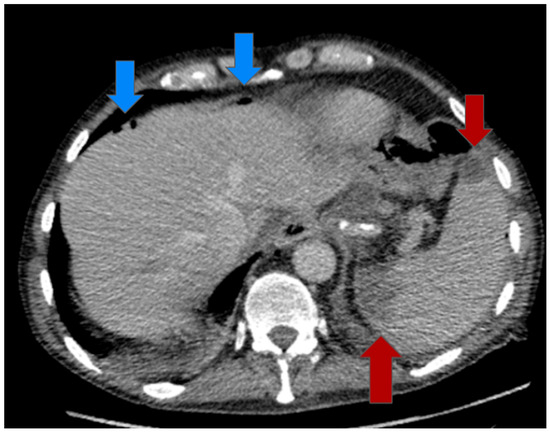

2.2. Multimodal Approach and Treatment

2.3. Postoperative Course